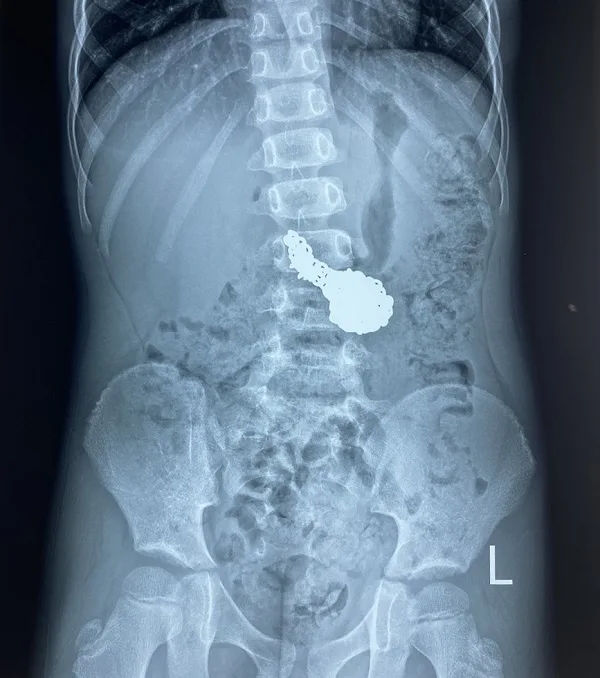

Qua thăm khám và chẩn đoán hình ảnh, các bác sĩ thấy hình ảnh một chiếc dây chuyền nằm trong ổ bụng bé. Do dây chuyền là một vật sắc nhọn nên cần phải gây mê để nội soi tránh những biến chứng xảy ra. Sau khi gắp thành công sợi dây truyền ra khỏi ổ bụng bé, sức khỏe của bệnh nhi bình thường và ra viện.

Điều may mắn là gia đình phát hiện và đưa cháu đến viện kịp thời, sợi dây chuyền bạc vẫn nằm ở dạ dày, chưa xuống đến hành tá tràng và ruột non nên chưa gây ra những biến chứng nguy hiểm như tắc ruột, ảnh hưởng nghiêm trọng đến tình trạng sức khỏe cháu bé.